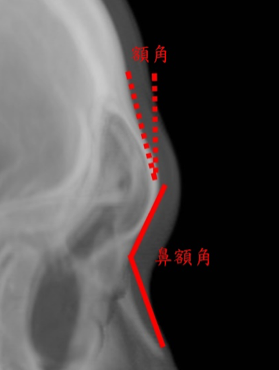

- 額頭的結構上需要考慮額角和鼻額角在性別上的差異:

- 額角˚

男性: 10±4˚

女性: 6±5˚ - 鼻額角˚

男性: 130±7˚

女性: 134±7˚